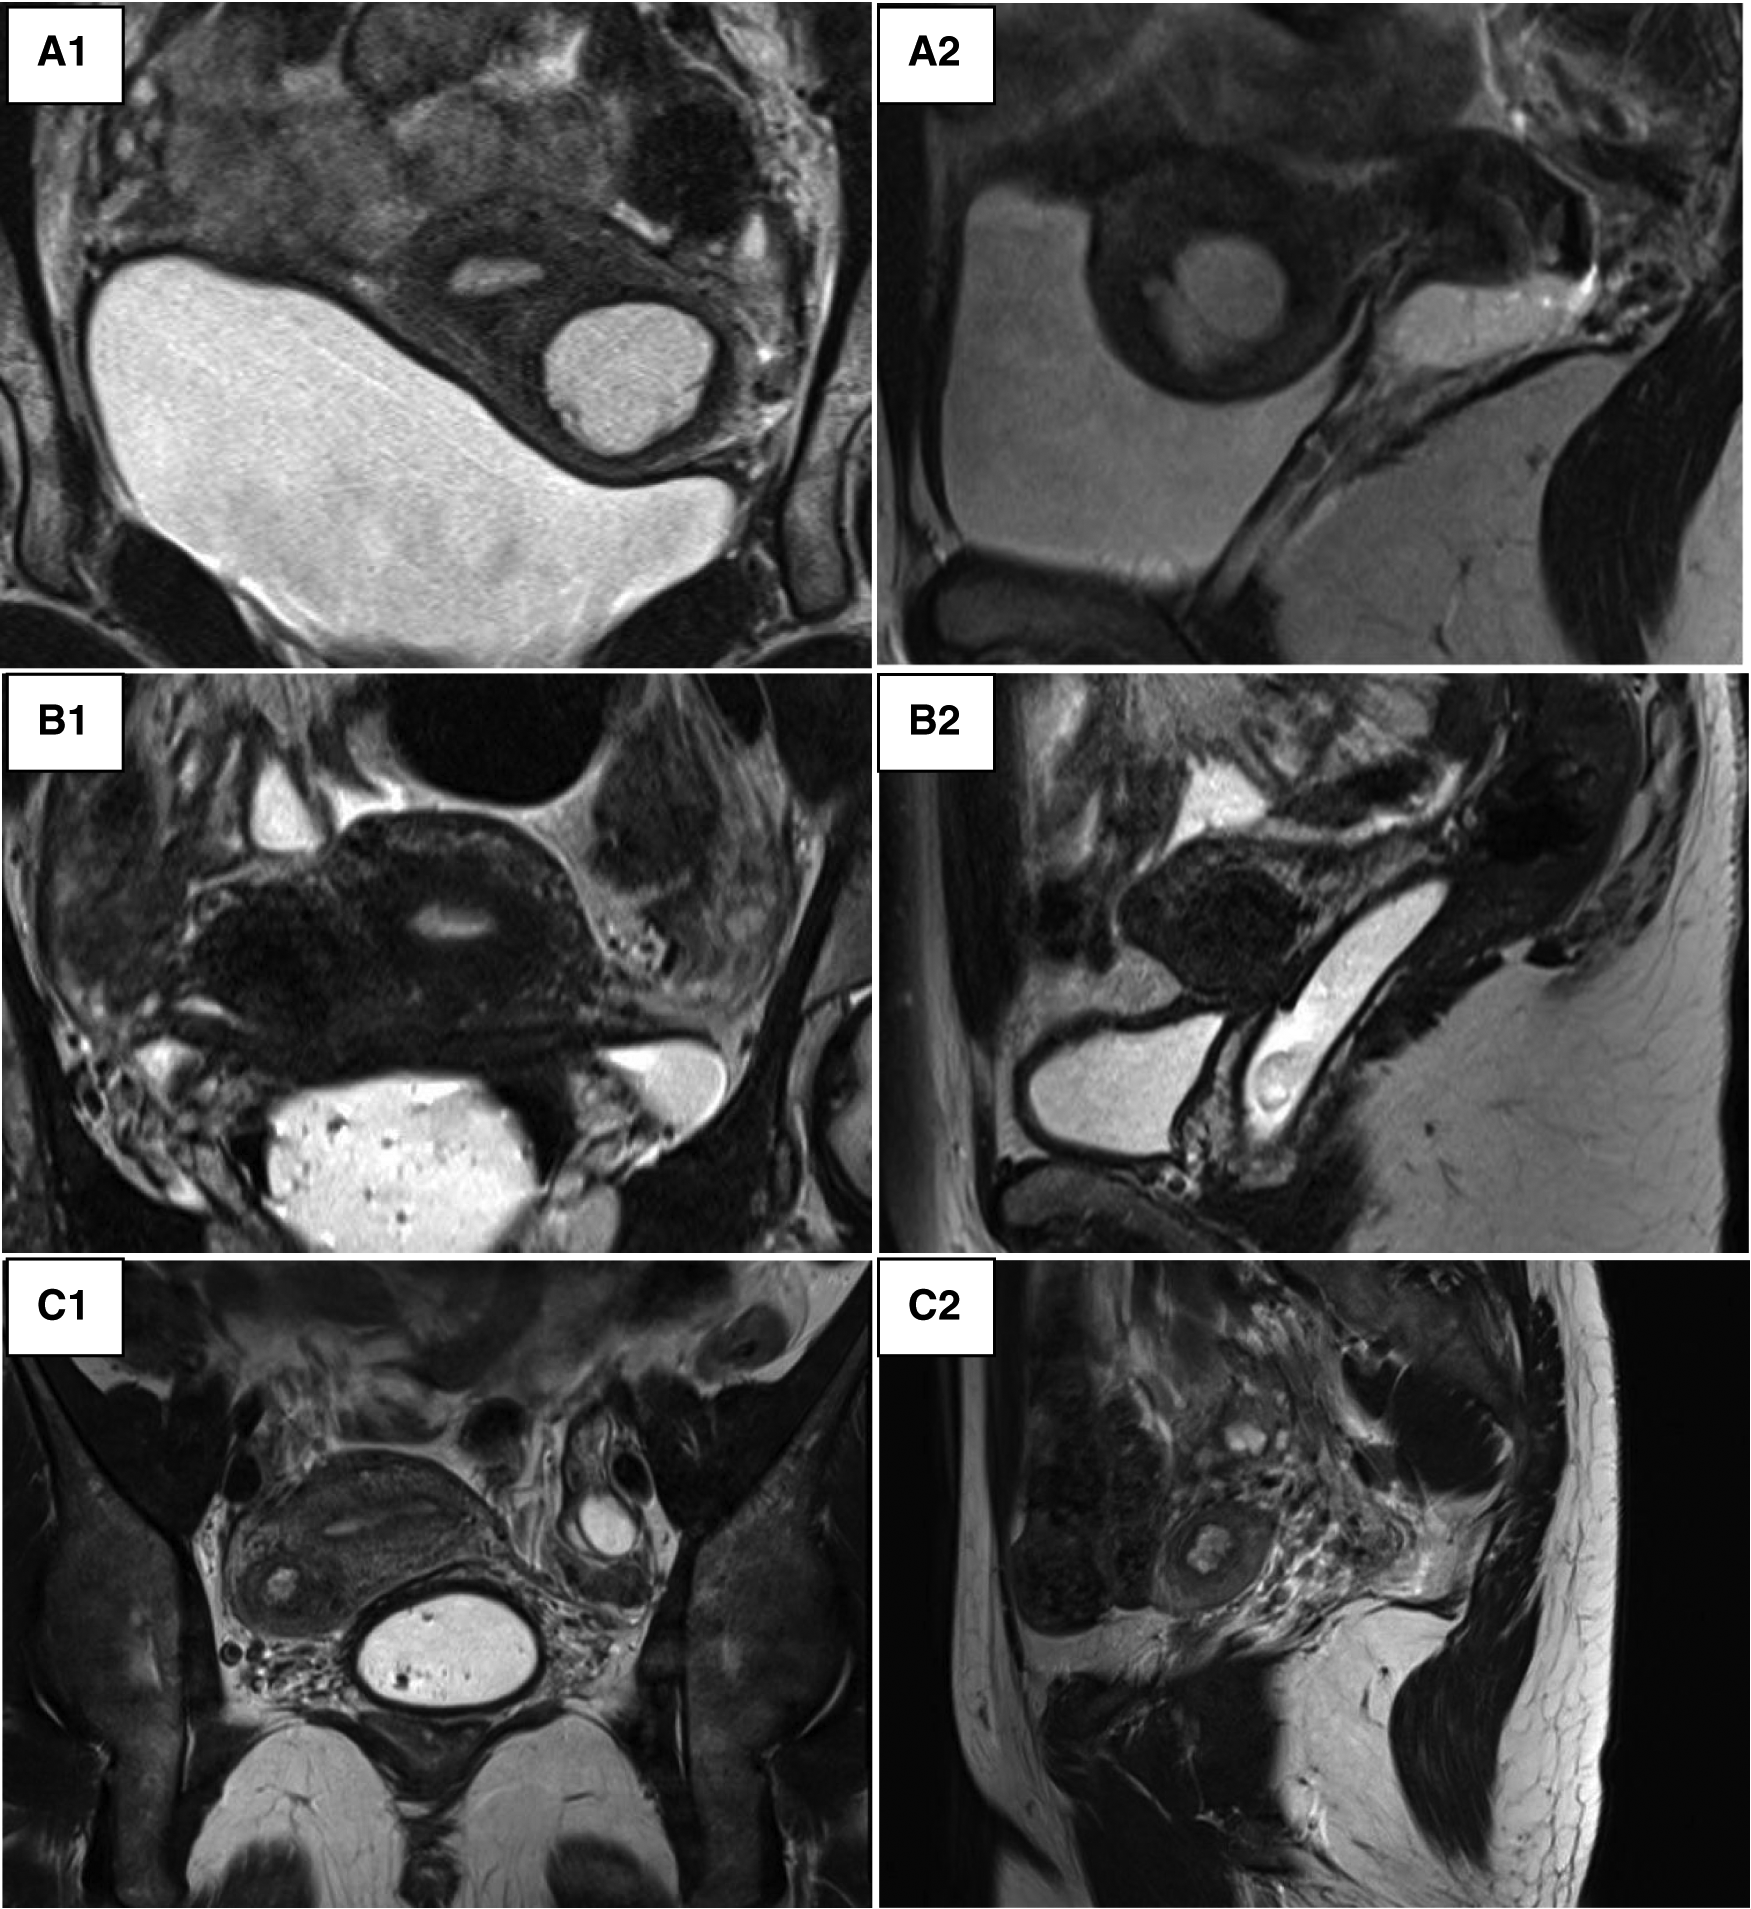

In addition to an ultrasound, all patients in our series underwent an MRI in order to have a precise description of the lesion (Figure 2). The lesion always had the same characteristics: the mass was isolated and composed of an external thick ring which had the same signal intensity as the junctional zone and regular boundaries. Its contents had a spontaneously hyper-intense signal on T1, T1 fat sat and T2-weighted images speaking for a haemorrhagic material. The rest of the genital and urinary tract was normal across all nine patients.

Figure 2. Pelvic MRI. (A) Patient 3_round mass in the left anterior myometrial wall suggestive of an accessory endometrial cavity within. (A1) T2-weighted coronal image. (A2) T2-weighted left lateral sagittal cut. (B) Patient 4_a round mass in the right anterior myometrial wall. (B1) T2-weighted coronal image. (B2) T2-weighted right lateral sagittal cut. (C) Patient 5_round mass in the right anterior myometrial wall. (C1) T2-weighted coronal image. (C2) T2-weighted right lateral sagittal cut.